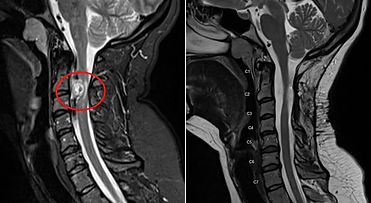

Dr. Srivatsan T V provides specialized management for a wide range of neurological and spinal conditions. Treatments are performed using advanced techniques such as neuroendoscopy, keyhole surgery, neuronavigation-guided precision surgery, and O-arm guided spine surgery. Wherever appropriate, minimally invasive approaches are chosen to help reduce discomfort, shorten recovery time, and improve long-term outcomes.